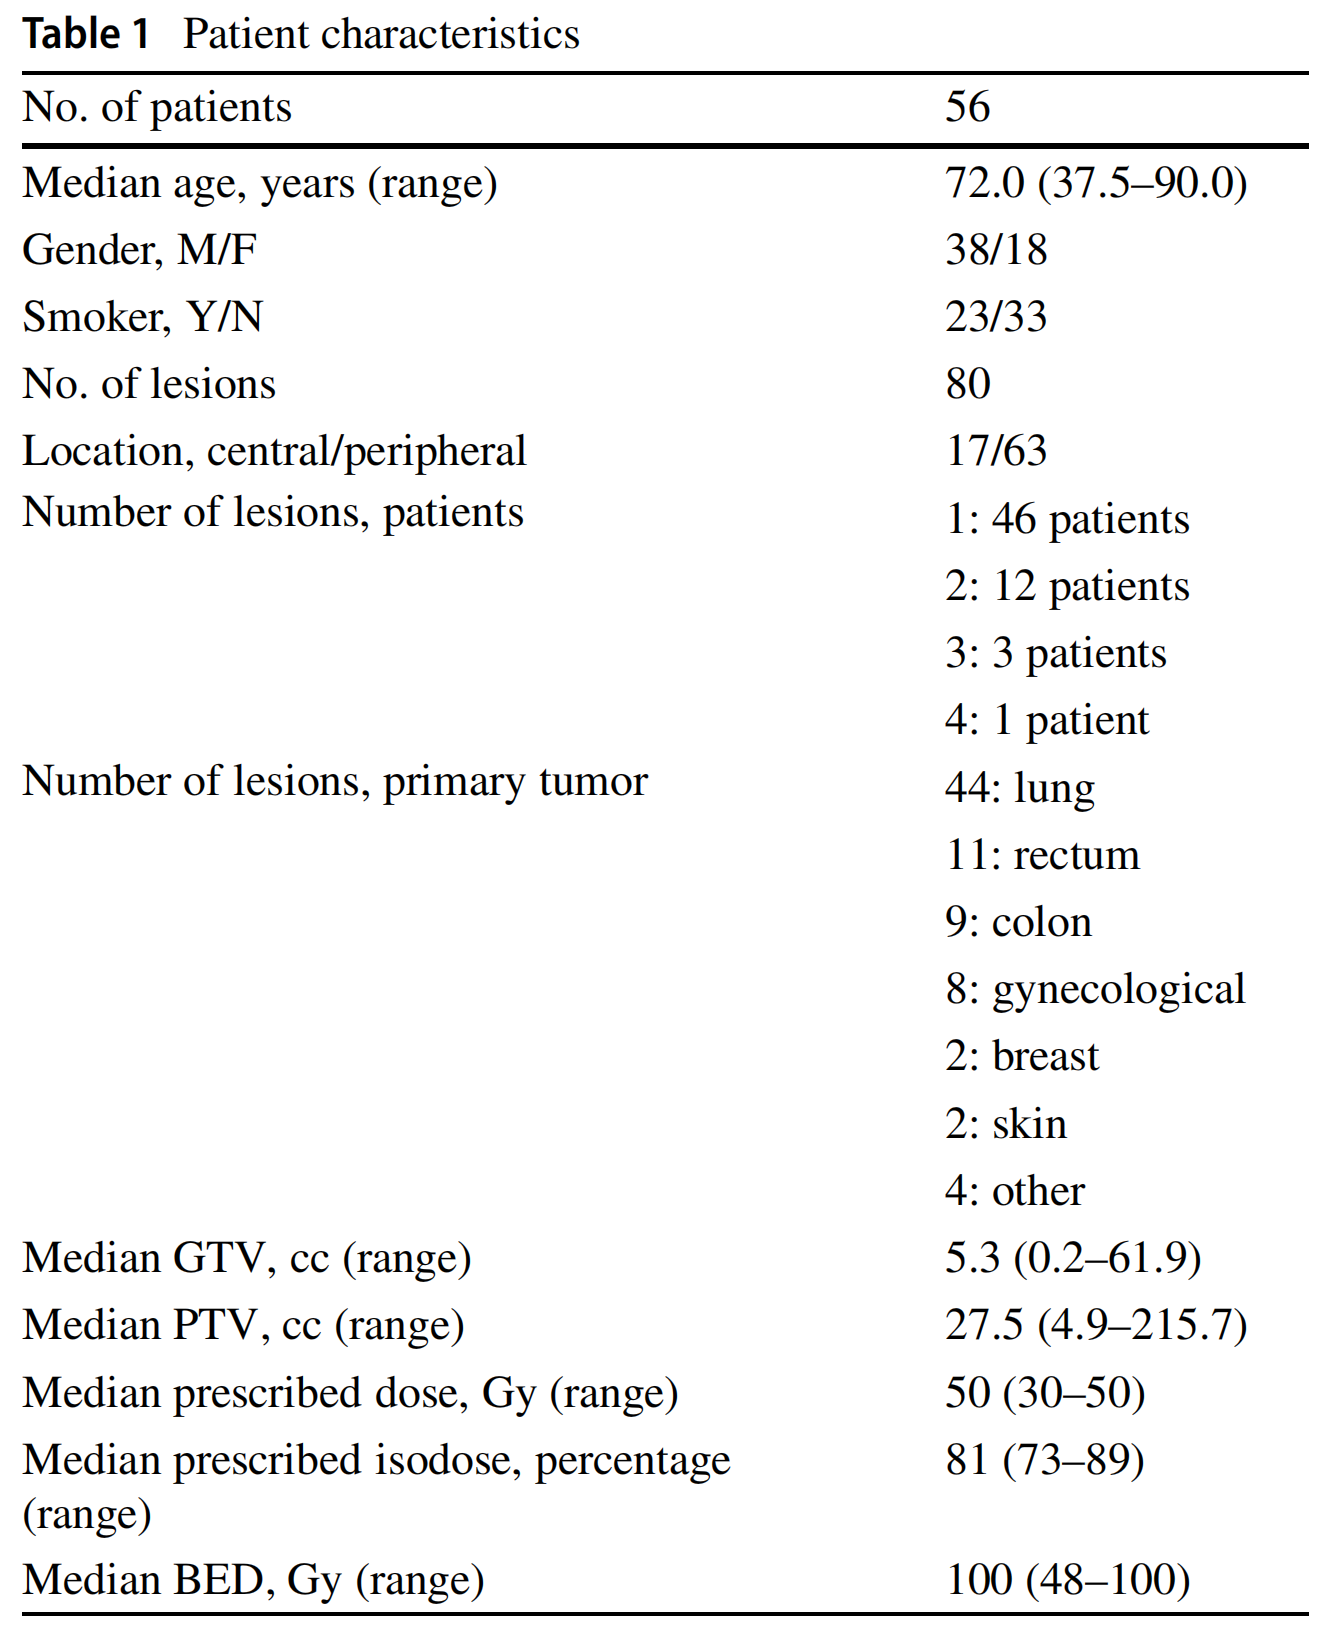

大多数转移瘤来自肺(44个转移瘤)和结直肠(20个转移瘤)肿瘤。在组织学方面,大多数是腺癌(35个病变),其次是鳞状细胞癌(7个病变)。表1报告了患者的特征。

以下是根据表格内容对患者特征的分析:

-

患者数量 (No. of patients): 共有56名患者参与了这项研究。

-

年龄 (Median age, years): 患者的中位年龄是72岁,年龄范围从38岁到90岁。

-

性别 (Gender, M/F): 其中38名为男性,18名为女性。

-

吸烟状况 (Smoker, Y/N): 23名患者是吸烟者,而33名患者不是。

-

病变数量 (No. of lesions): 总共分析了80处病变。

-

病变位置 (Location, central/peripheral): 病变位置分为中心型和周围型,分别是17处和63处。

-

患者病变数量 (Number of lesions, patients):

- 有46名患者有1处病变。

- 12名患者有2处病变。

- 3名患者有3处病变。

- 1名患者有4处病变。

-

原发肿瘤的病变数量 (Number of lesions, primary tumor):

- 44处病变源自肺部肿瘤。

- 11处源自直肠肿瘤。

- 9处源自结肠肿瘤。

- 8处源自妇科肿瘤。

- 2处源自乳腺癌。

- 2处源自皮肤肿瘤。

- 4处源自其他类型的肿瘤。

-

肿瘤体积 (Median GTV, cc): 肿瘤的中位总体积(Gross Tumor Volume, GTV)是5.3立方厘米(cc),范围从0.2到61.9 cc。

-

计划治疗体积 (Median PTV, cc): 计划治疗体积(Planning Target Volume, PTV)的中位数是27.5 cc,范围从4.9到215.7 cc。

-

处方剂量 (Median prescribed dose, Gy): 中位处方剂量是50 Gy,范围从30到50 Gy。

-

处方等剂量百分比 (Median prescribed isodose, percentage): 中位处方等剂量百分比是81%,范围从73到89%。

-

生物等效剂量 (Median BED, Gy): 生物等效剂量(Biological Equivalent Dose, BED)的中位数是100 Gy,范围从48到100 Gy。

这些患者特征为研究提供了重要的背景信息,有助于理解研究的参与者群体,并可能对分析研究结果和解释治疗响应的影响因素提供线索。例如,吸烟状况可能与肺癌的发展有关,而肿瘤的位置、数量和体积可能会影响SBRT治疗计划和治疗结果。